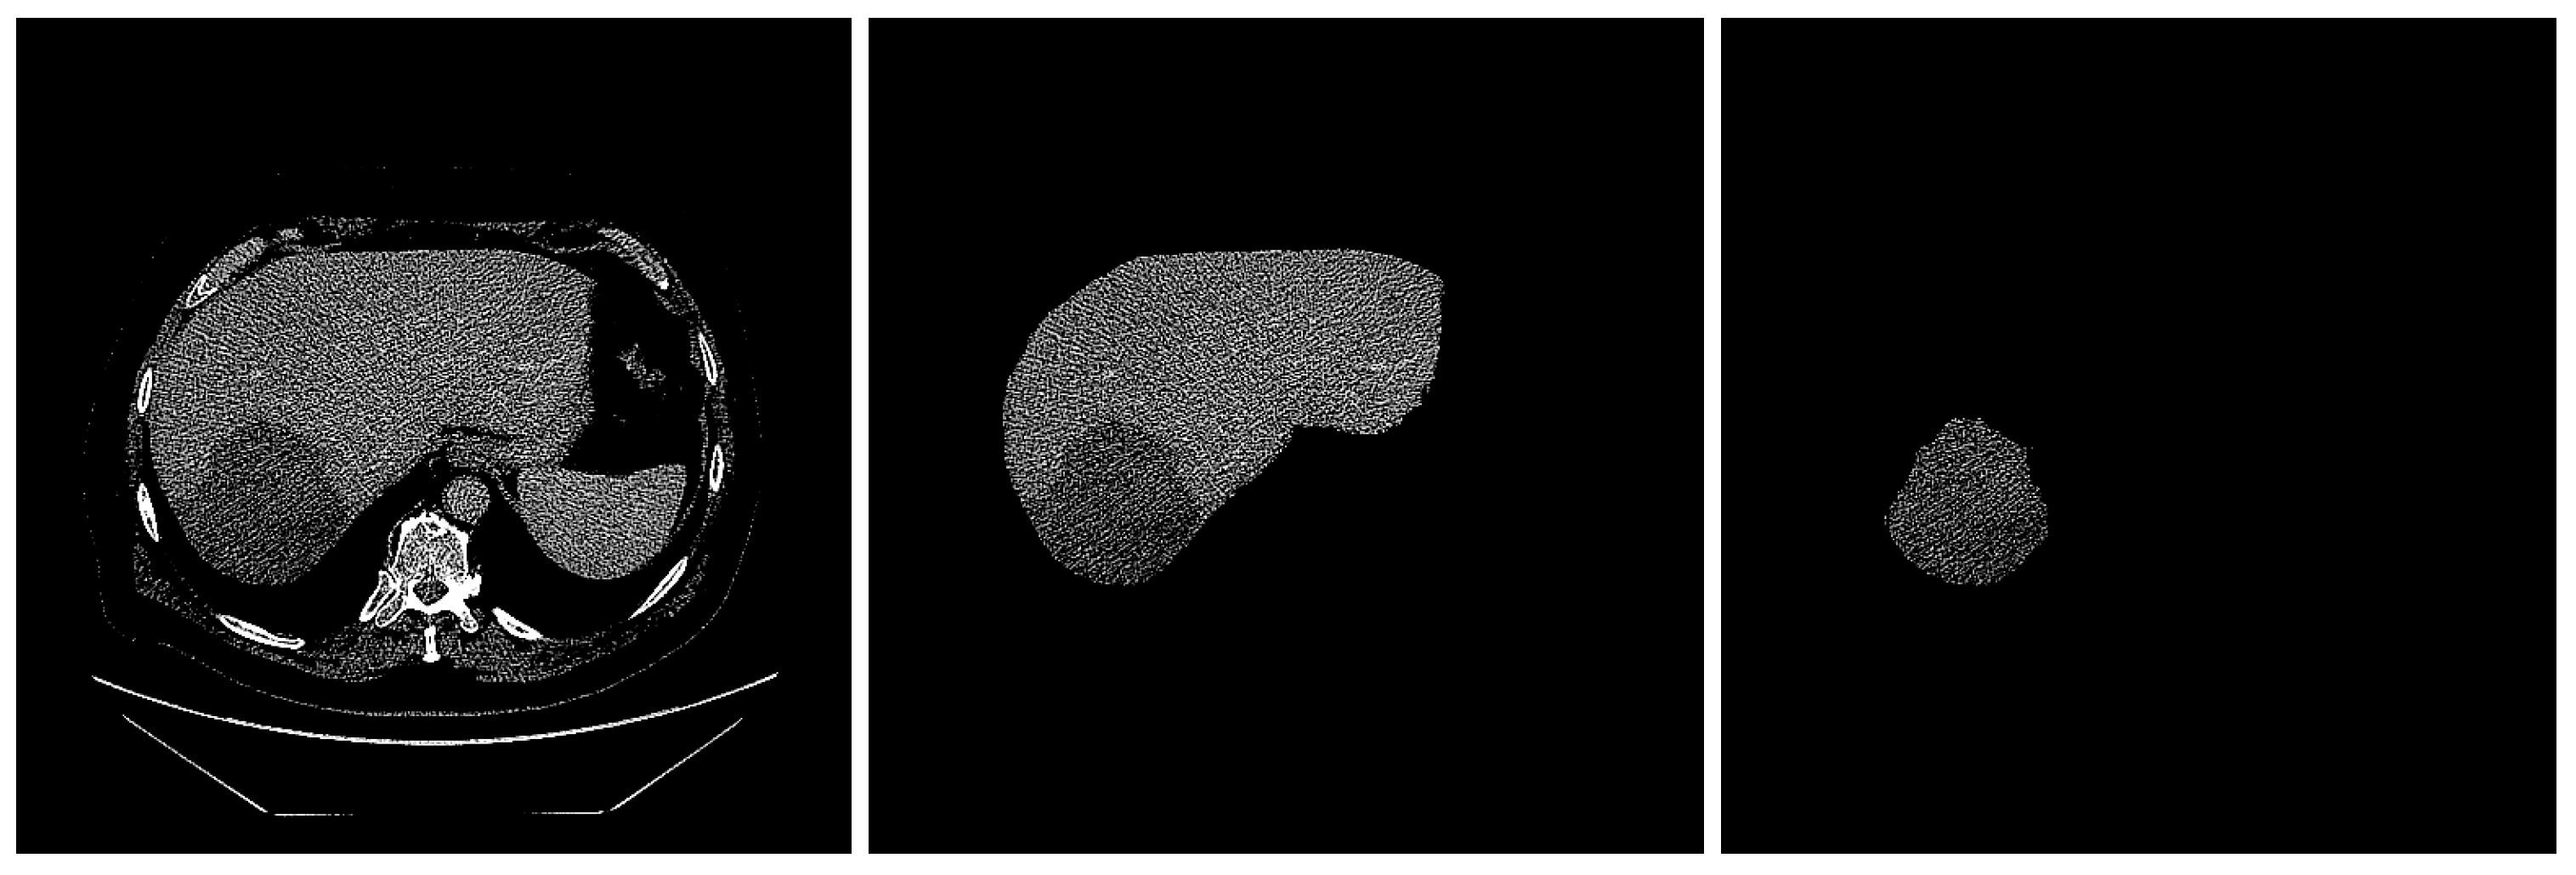

Image segmentation is the procedure by which an image is partitioned into significant regions, with distinct attributes assigned to individual pixels. The performance of image-segmentation methods is contingent upon various factors, including the type of image, manner of application, size, and color intensity. Two radiologists, each with three years of experience in abdominal CT diagnosis, used the Radiology Informatics Laboratory Contour (RIL-Contour) software [19] to segment the ROI in the images manually. Figure 2 shows a sample CT scan of a liver tumor and the segmentation.

Figure 2.

The segmentation of liver. (left) Original image with HCC masses inside. (middle) Liver segmented. (right) Tumor segmented.